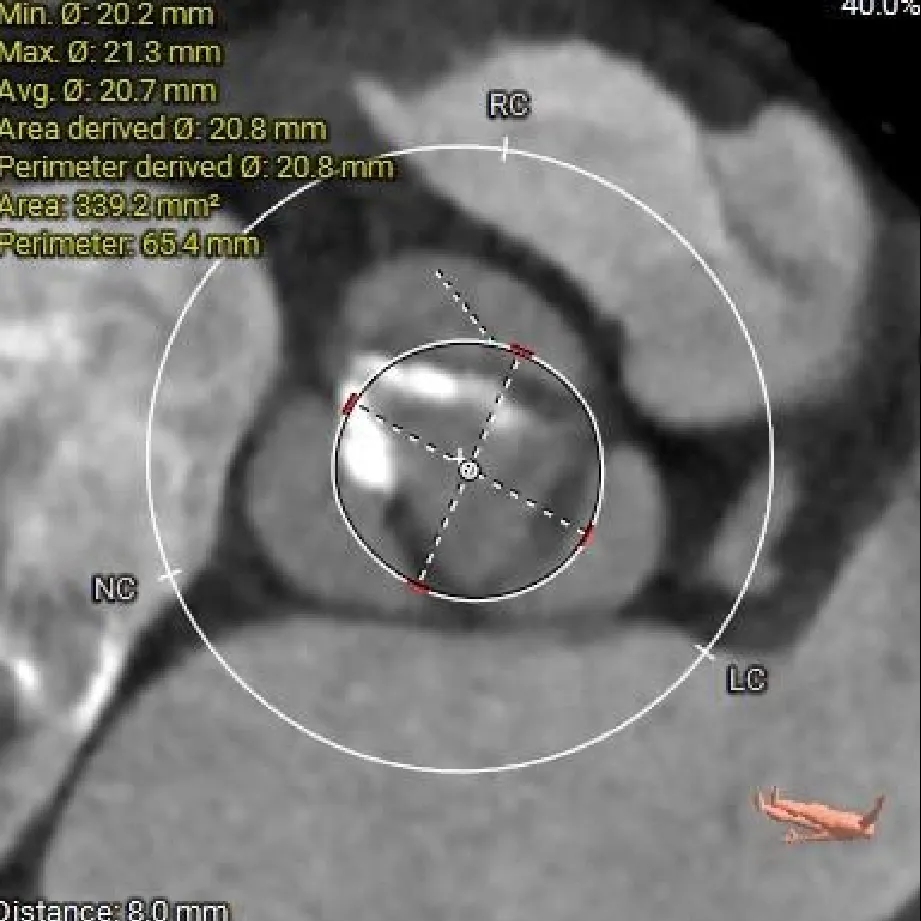

主动脉根部测量

Left Coronary

11.5mm

LCA & Leaflet

12.2mm<13.0mm

Right Coronary

10.5mm

RCA & Leaflet

13.3mm<13.5mm

-

左、右冠脉高度偏低

双侧瓣叶偏长

结合SOV、STJ内径评估冠脉风险适中,结合球扩情况充分评估